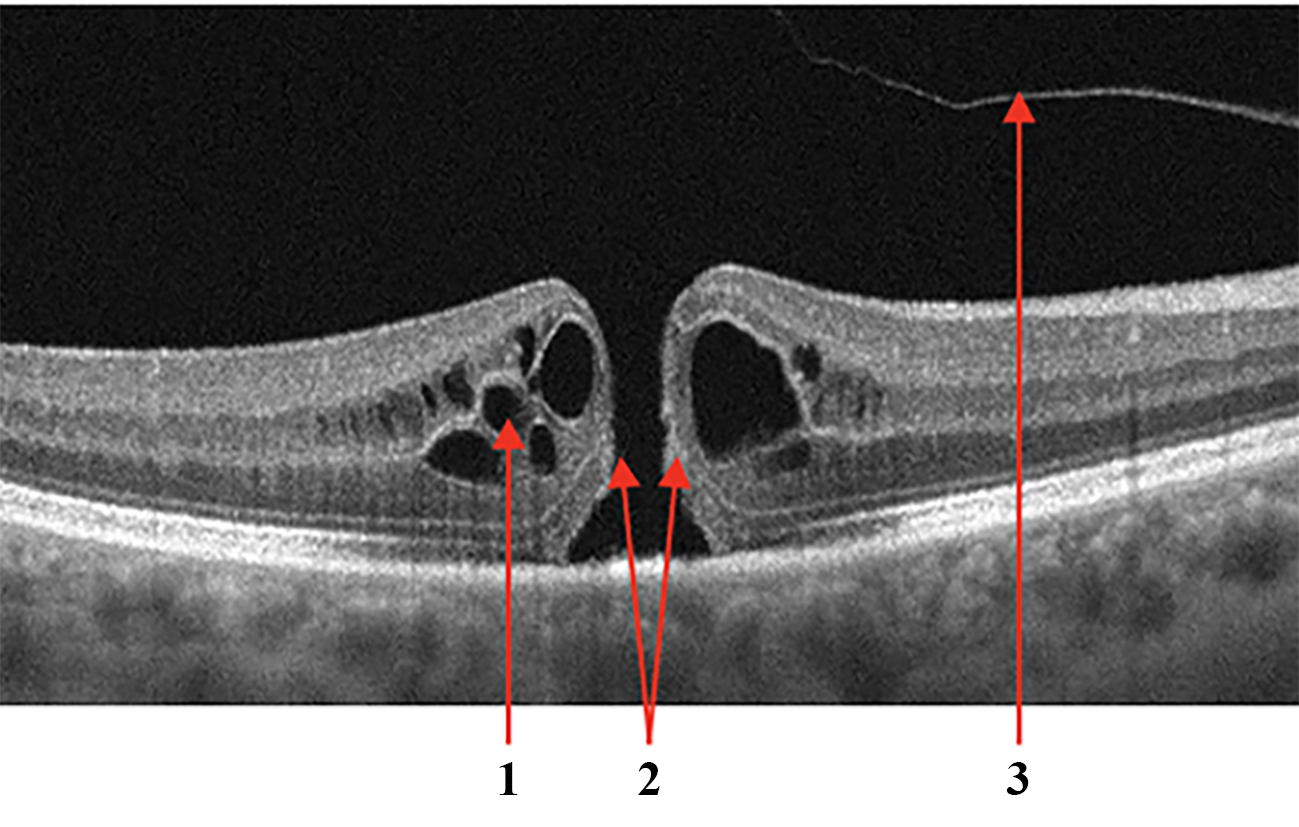

Vitreomacular Interface Disease

VID is a term used to describe a group of diseases resulting from the pathologic course of the normal age-associated process of a posterior vitreous detachment. Usually, the process is completed without retinal deformation. However, vitreo-retinal traction occurs in cases of adhesion between the retina and vitreous body, which can lead to macular tears, cysts, or holes developing [38].

• When pathologic adhesion of the posterior hyaloid to the retinal interface forms, progressive posterior vitreous detachment causes axial traction of the inner limiting membrane, formed by Müller cell end feet that deforms the retinal tissue, Fig.6a.

• Macular retinal hole is a complete defect in the inner layers of the retina that extends to the RPE, Fig.6b. IRF appears as different-sized cavities with hyporeflective contents. In macular retinal tears, the intraretinal fluid is contained within the borders of the tear [39].

• One of the variants of MH with preservation of the integrity of the photoreceptor layer is a lamellar tear of the neurosensory retina, Fig.6c. The condition is often asymptomatic and requires no treatment, but regular monitoring by a medical retina specialist is advised.

Refer to caption

((a)) Vitreomacular traction syndrome

((b)) Retinal interface disorder, complete macular tear

((c)) Lamellar tear

Figure 6: Vitreomacular Interface Disease (VID). Vitreomacular traction syndrome (a): 1 - Posterior hyaloid membrane, 2 - Vitreomacular adhesion zone, 3 - Emerging neurosensory retinal defect; Retinal interface disorder (b): 1 - intraretinal fluid (IRF), 2 - Edges of the tear, 3 - detached posterior hyaloid membrane; Lamellar tear (c).